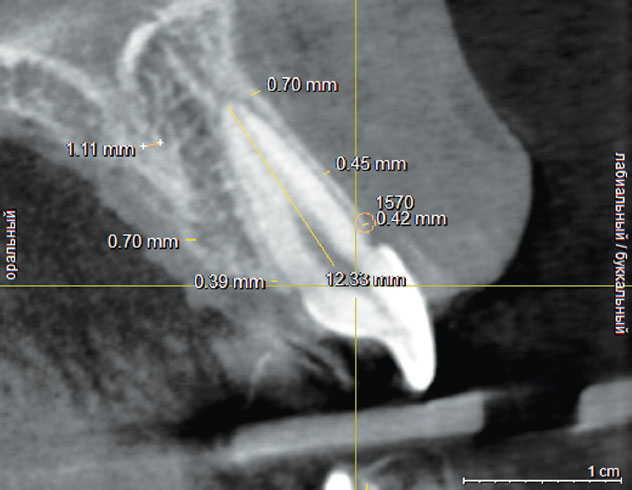

Рис. 1. Измерение длины корня зуба 1.1 на сагиттальном срезе, измерение толщины компактной пластинки с вестибулярной стороны в 3 областях: В — верхушка корня, С — средняя часть корня, Ш — шейка

Fig. 1. Tooth 1.1 root length measurement on a sagittal slice, compact plate thickness measurement in the vestibular part in three areas: В, apex; С, middle; Ш, neck